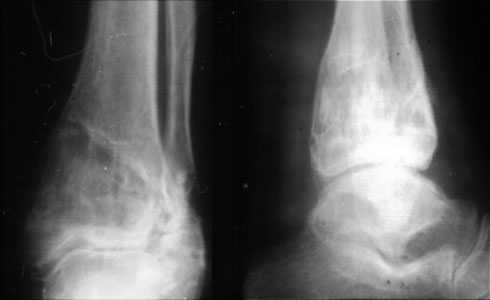

Аппаратом можно сделать все минимально инвазивно и травматично, вырастить клиновидный регенерат после чрескожной остеотомии через один или два разреза 0,5 см. В приложении похожий по локализации случай, только более давние последствия травмы с замыканием части зоны роста, деформация побольше, плюс укорочение голени было.